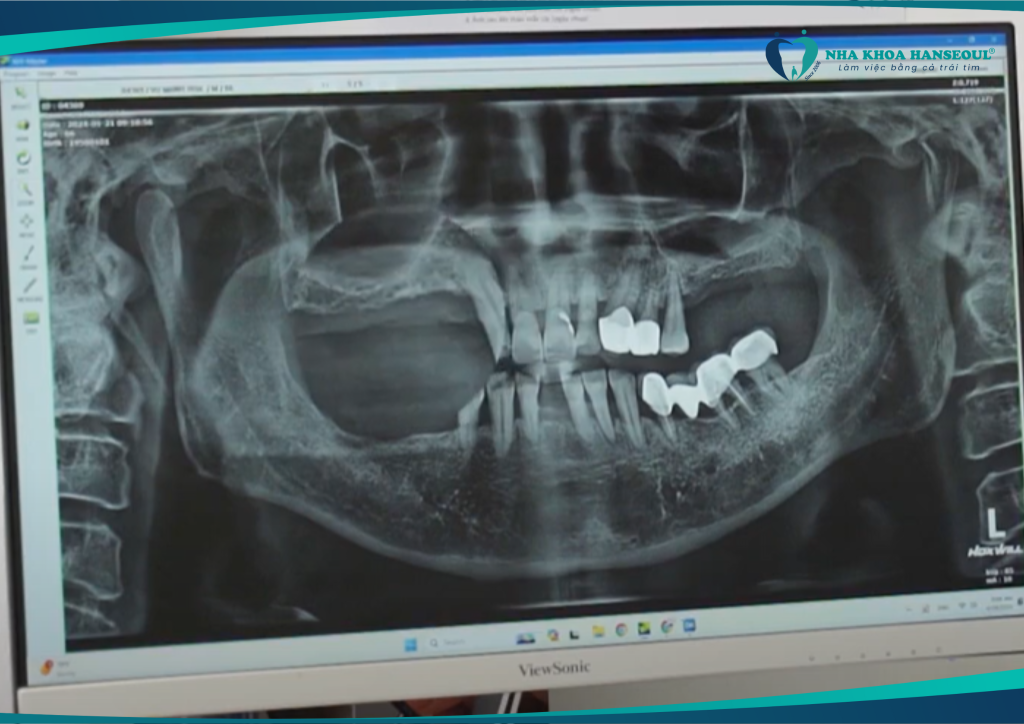

Sau khi được các bác sĩ thăm khám và chụp phim kỹ lưỡng, chú được chỉ định phục hình toàn diện bằng công nghệ cấy ghép răng Implant Hansafe. Đây là giải pháp hiện đại giúp phục hồi răng mất an toàn, không đau, ăn nhai như răng thật.